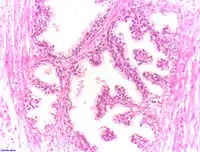

Adénocarcinome prostatique

Adénocarcinome ; tissus indifférenciés

Invasion périneurale par un adénocarcinome prostatique. HE, x400

Score de Gleason

La structure tissulaire des cancers de la prostate varie des formes différenciées (cellules cancéreuses ressemblant aux cellules saines), dite de grade 1, aux formes les moins différenciées (cellules cancéreuses présentant beaucoup de caractères atypiques par rapport aux cellules saines), dite de grade 5.

Plusieurs grades peuvent se rencontrer au sein d'un même tissu. Le score de Gleason est calculé de la façon suivante : on additionne les deux grades les plus représentés de la tumeur. Le premier chiffre représentant le score du contingent le plus représenté. Ainsi 4+3 est plus péjoratif que 3+4

Si la somme est de 6 ou moins, le cancer est dit bien différencié, donc de meilleur pronostic ; 7 : le cancer est moyennement différencié ; 8 ou plus : le cancer est peu différencié, donc de moins bon pronostic.